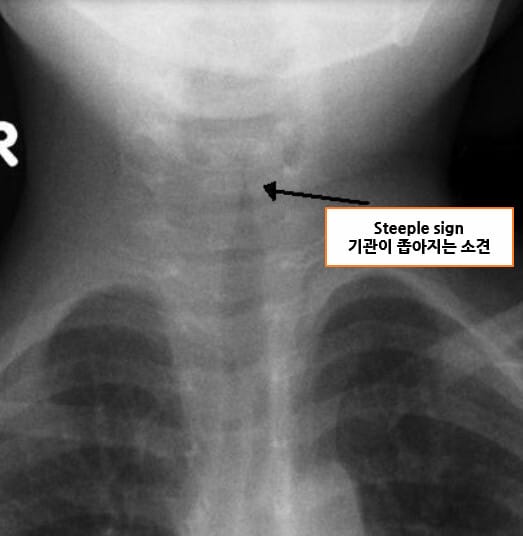

– 임상 증상으로 진단; 흉부·경부 X선에서 ‘steeple sign’이 보일 수 있음

– 중증도 평가: Westley score (천명, 공기 흐름, 청색증, 의식 수준 등)